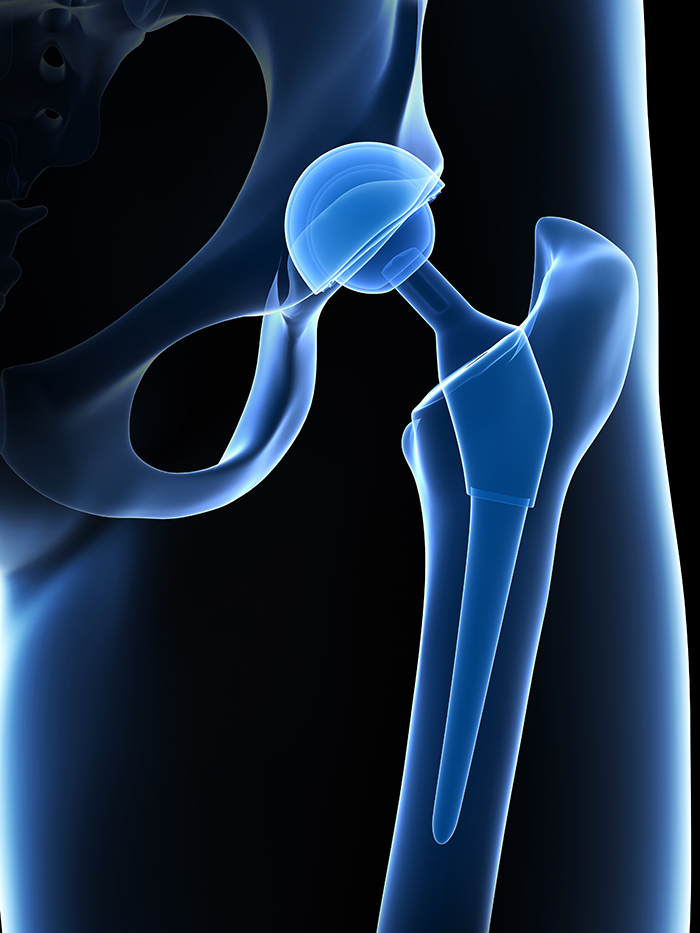

Total hip replacement (THR) is a surgical procedure in which the damaged cartilage and bone is removed from the hip joint and replaced with artificial components. The hip joint is one of the body’s largest weight-bearing joints, located between the thigh bone (femur) and the pelvis (acetabulum). It is a ball and socket joint in which the head of the femur is the ball and the pelvic acetabulum forms the socket. The joint surface is covered by smooth articular cartilage which acts as a cushion and enables smooth movements of the joint.

The surgery is performed under general anesthesia. During the procedure a surgical cut is made over the hip to expose the hip joint and the femur is dislocated from the acetabulum. The surface of the socket is cleaned and the damaged or arthritic bone is removed using a reamer. The acetabular component is inserted into the socket using screws or occasionally bone cement. A liner made of plastic, ceramic or metal is placed inside the acetabular component. The femur or thigh bone is then prepared by removing the arthritic bone using special instruments, to exactly fit the new metal femoral component. The femoral component is then inserted to the femur either by a press fit or using bone cement. Then the femoral head component made of metal or ceramic is placed on the femoral stem. All the new parts are secured in place using special cement. The muscles and tendons around the new joint are repaired and the incision is closed.